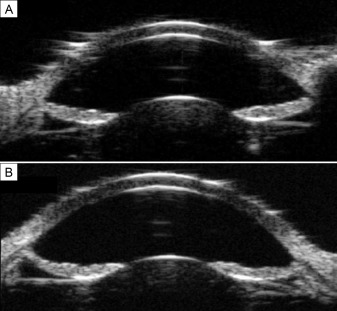

실제로 전방이 깊고 수정체가 편평한 젊은 근시 환자에서 색소녹내장이 잘 발생한다는점,

수정체가 두꺼워지는 노년층에서는 색소녹내장이 오히려 줄어든다는점 등이,

홍채와 섬모체소대와의 마찰에 의해 색소분산이 발생한다는 점의 근거가됩니다.